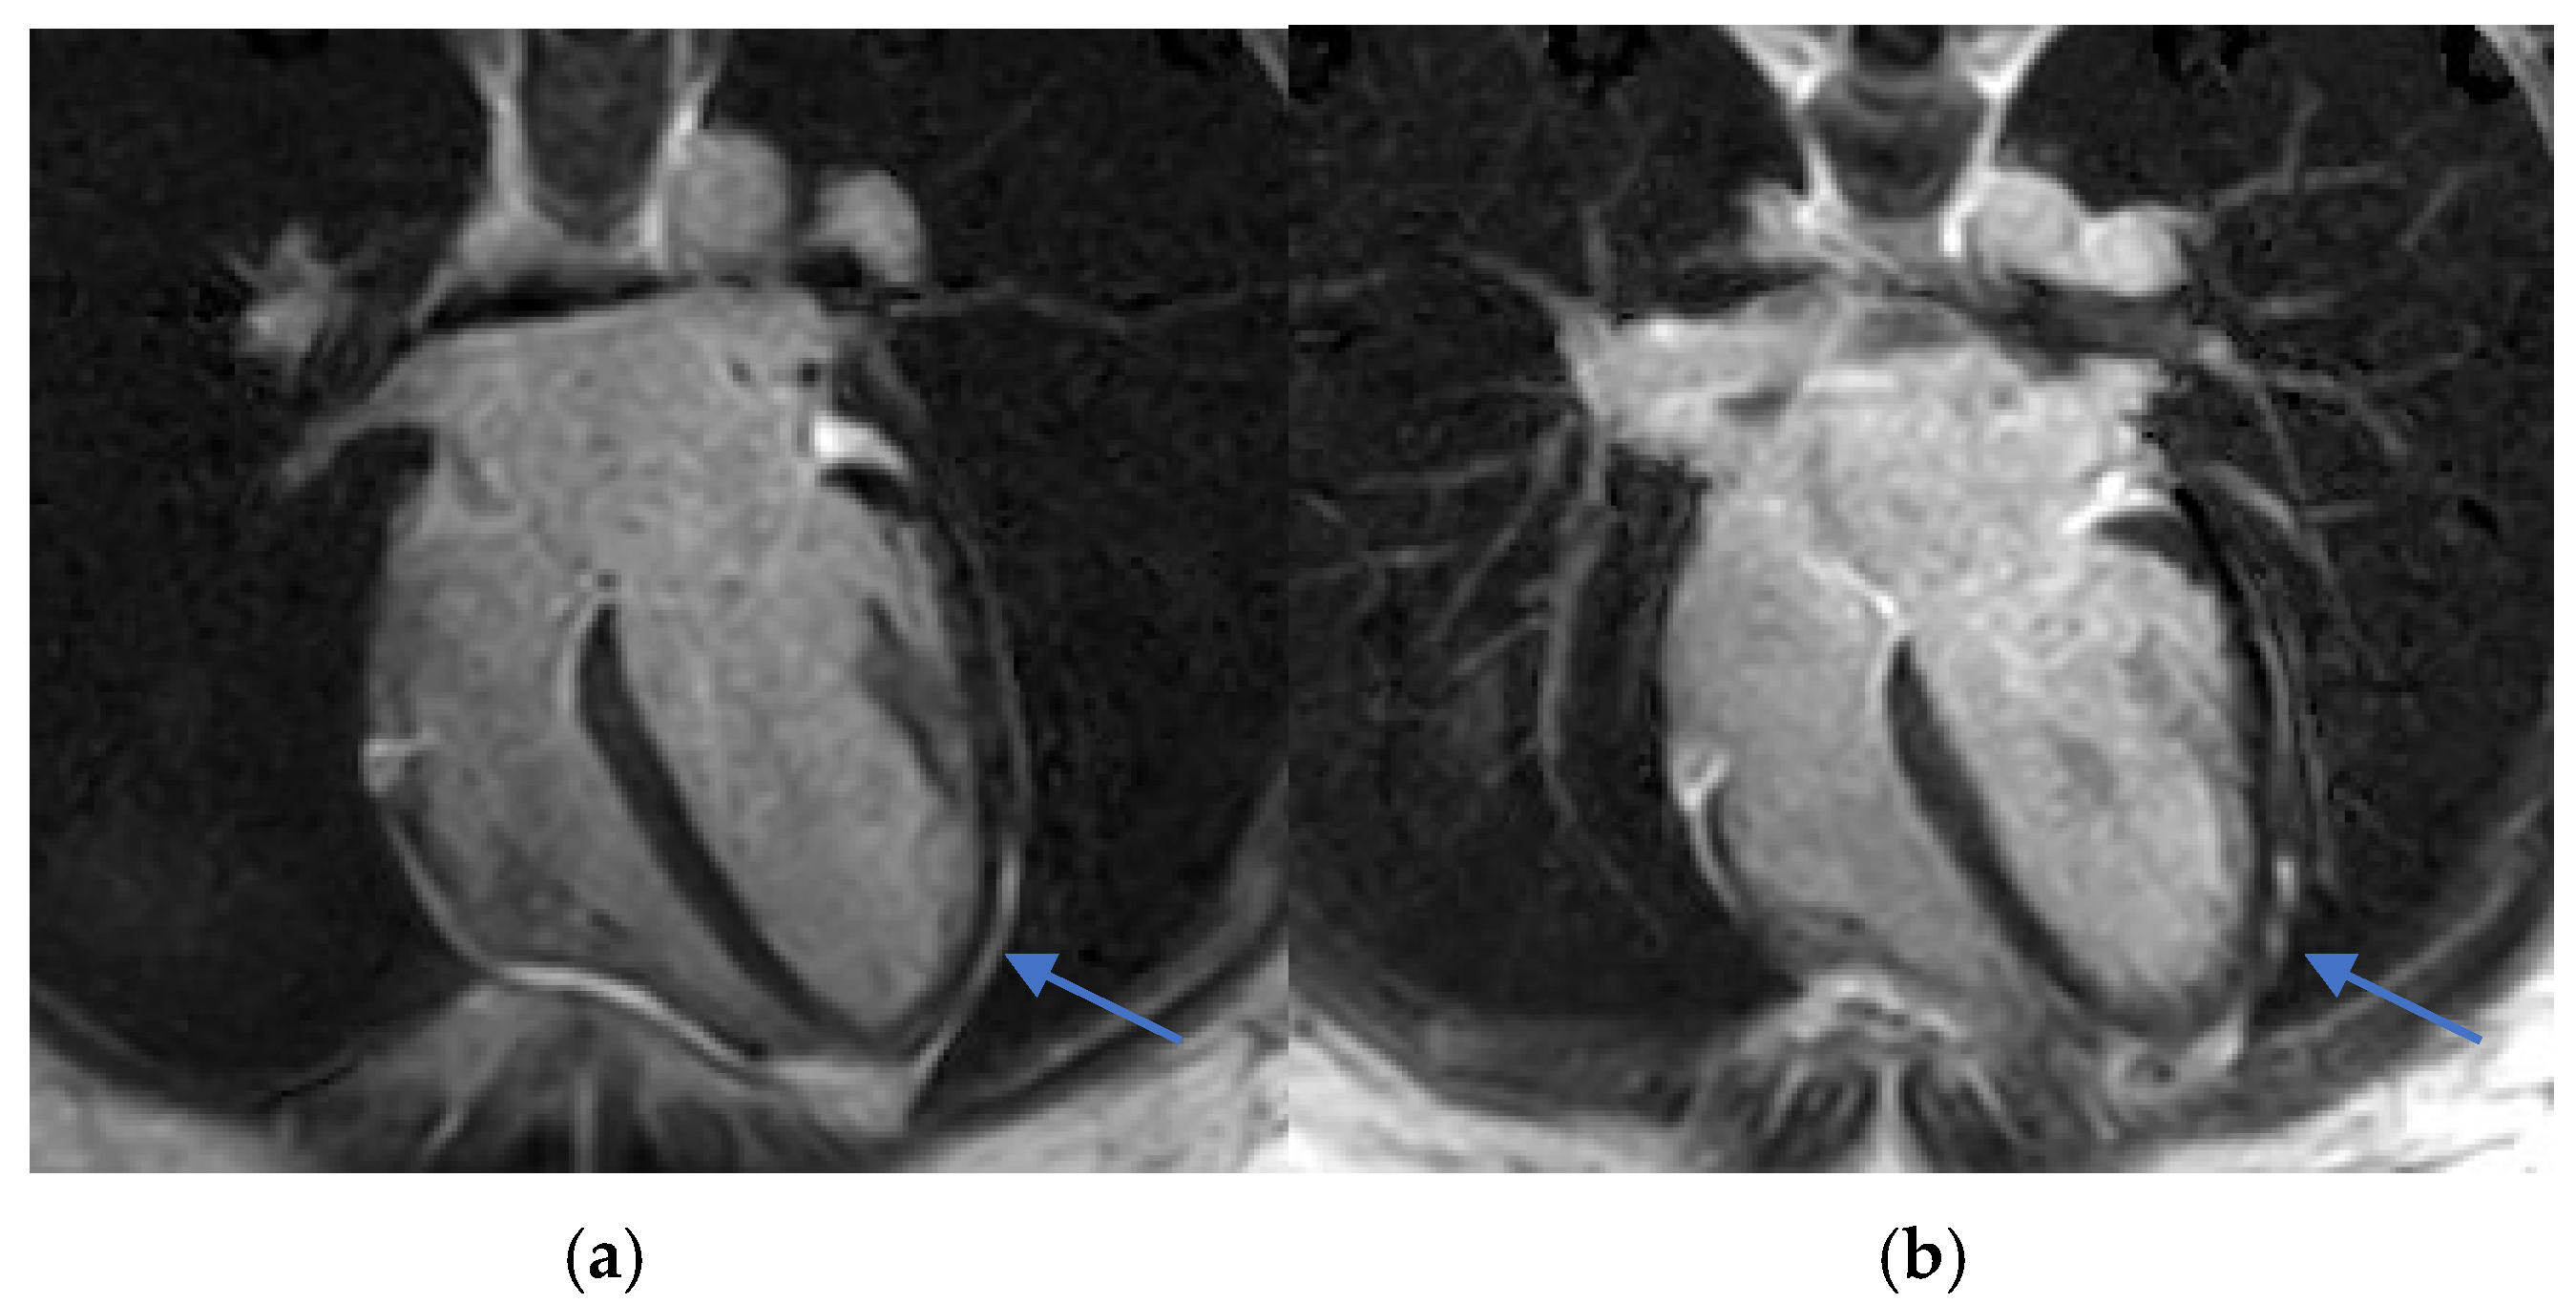

The patient’s medical history was notable for metastatic pheochromocytoma, initially managed with a left adrenalectomy in 2017. After surgery, she remained under routine surveillance until August 2022, when she was diagnosed with skeletal metastasis confirmed by dihydroxyphenylalanine positron emission tomography/computed tomography (DOPA PET/CT) (Figure 1). Since the diagnosis, her disease has been managed with monthly somatostatin analog therapy (Lanreotide 120 mg), and she has remained in stable condition. Additionally, she had a history of papillary thyroid carcinoma (stage I, T1aN0M0), treated with right partial thyroidectomy in 2021, and was maintained on levothyroxine therapy. The patient had no history of smoking, cardiovascular disease, or autoimmune conditions.

Figure 1. DOPA PET/CT sagittal images showing increased radiotracer uptake in the skeletal system, consistent with skeletal metastases from metastatic pheochromocytoma. The images demonstrate significant involvement in the spine and pelvis.